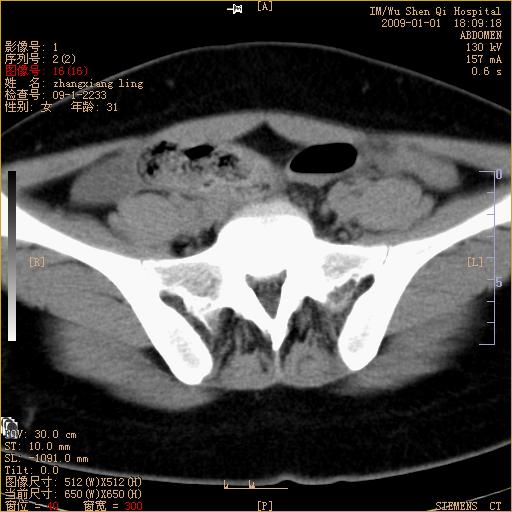

标题: CT17527:F31Y,腹痛伴血便9小时 [打印本页]

标题: CT17527:F31Y,腹痛伴血便9小时

升结肠肠壁不规则增厚,肠腔狭窄,考虑升结肠占位,建议增强扫描

升结肠肠壁不规则增厚,肠腔狭窄,考虑升结肠占位,建议增强扫描,不除外肠套叠.

升结肠肠壁不规则增厚,似呈同心圆改变,其有积液。结合病史首先考虑肠套叠伴肠壁坏死可能性大,结肠肿瘤待排。

患者已手术,结果肠系膜血栓形成肠坏死

结果:患者已手术,结果肠系膜血栓形成肠坏死。回过头再看局部肠壁增厚有分层(高密度坏死及低密度水肿)表现。